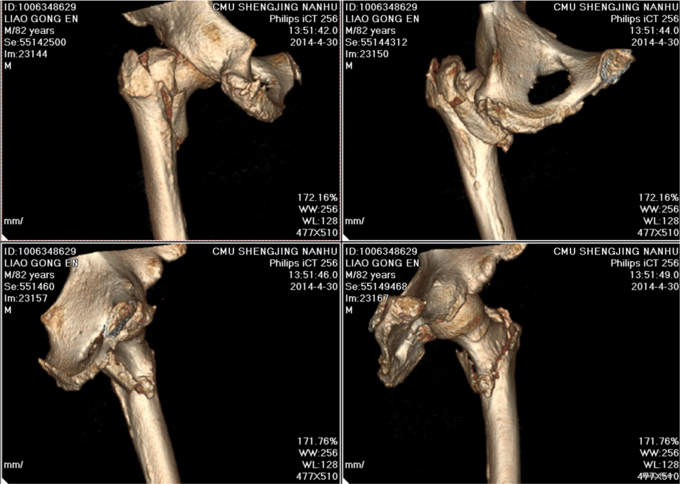

患者2014-04-27日上午9时摔倒后左髋部疼痛肿胀、活动受限,不能站立行走,急来中国医科大学附属盛京医院急诊科,急诊予以行辅助检查,左下肢DR提示:左股骨粗隆间骨折,现患者为求进一步诊治,以“左股骨粗隆间骨折”为诊断收入我科。患者自受伤以来一般状态可,无发热,无头晕、呕吐,无胸闷、心悸呼吸困难,无腹痛、腹泻,饮食可,睡眠可,二便正常。

左髋部未见明显肿胀及瘀斑,活动度减低,活动因疼痛受限,左髋部压痛阳性,叩击痛阳性,左下肢缩短畸形,缩短1cm,外旋80°。左膝及左踝关节活动无明显异常。双侧足背动脉搏动有力,肢体末梢血运良好,皮温正常。远端足趾感觉运动正常,